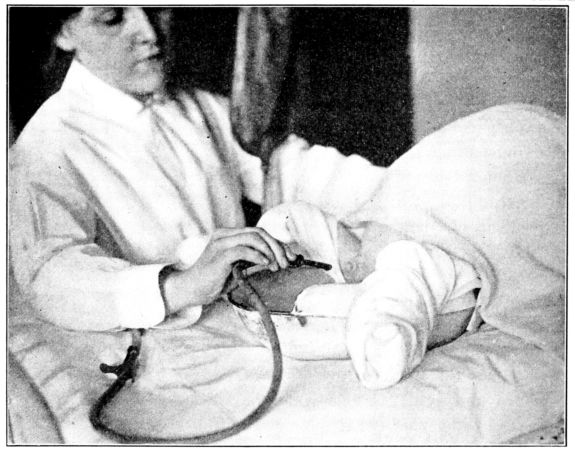

| 182. | Obtaining a fresh specimen of urine from the baby | 526 |

| 183. | Obtaining a 24–hour specimen of urine from the baby | 527 |